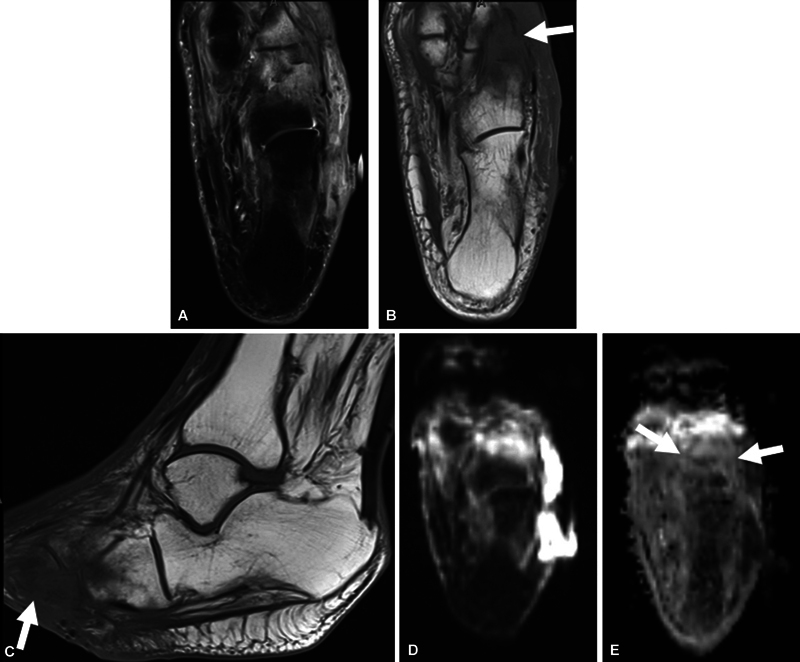

Objective  The aim of this study was to determine the sensitivity and specificity and inter-reader reliability of previously known "ghost sign" and "penumbra sign" on T1-weighted (T1W) imaging and "ghost sign" on apparent diffusion coefficient (ADC) map in osteomyelitis (OM) of the extremities. Materials and Methods  In this cross-sectional retrospective study, two fellowship-trained musculoskeletal readers blinded to final diagnosis of OM versus no OM were asked to report the penumbra sign and ghost sign on T1W images and ghost sign on ADC map, as well as diagnosis of OM. Cohen's kappa was used. Diagnostic performance measures including sensitivity, specificity, and accuracy were calculated. Results  A sample of 178 magnetic resonance imaging (MRI) scans of pathology-proven cases were included in this study, with 41 being positive for OM and 137 being negative for OM. There was a fair inter-reader agreement for imaging signs, and moderate agreement of 0.60 for OM. The sensitivities of the penumbra sign on T1W imaging, ghost sign on T1W imaging, and ghost sign on ADC map for OM are 3.7, 9.8, and 19.5%, respectively, while their respective specificities are 98.9, 97.8, and 94.5%, respectively. All three imaging signs showed a similar (good) accuracy of 76 to 78%. Conclusion  The ghost sign on ADC can be used as an additional marker for OM and is a similarly highly specific but a more sensitive sign for OM than the conventionally used penumbra sign and ghost sign on T1W imaging. Key Points The ghost sign on ADC can be used as a helpful indicator of osteomyelitis.Across two fellowship-trained musculoskeletal readers, there was a fair inter-reader agreement for imaging signs and moderate agreement for OM.The ghost sign on ADC is a similarly highly specific but a more sensitive sign for osteomyelitis than the conventionally used penumbra sign and ghost sign on T1W imaging. All three imaging signs showed a similar (good) accuracy of 76 to 78%.

Abstract Image